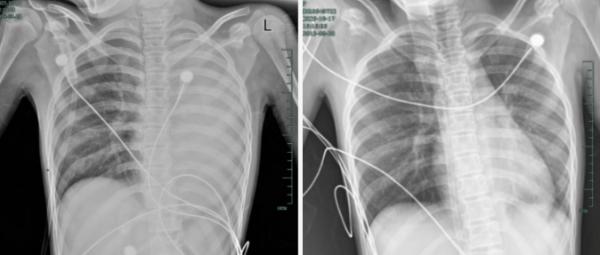

治疗前后影响对比,左肺从“白肺”到正常状态。

据介绍,笑笑一开始只是轻微咳嗽,发热到38℃,检查提示肺炎、肺不张,转诊到浙大四院儿科时,病情已经急剧恶化,出现呼吸急促、胸闷胸痛,体温38.5℃,只能靠5L/min的面罩吸氧维持血氧,胸片显示左肺已完全呈 “白肺” 改变,肺部炎症进展迅猛。